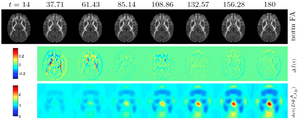

Longitudinal macaque developmental DTI atlas from postnatal day 14 to 180 as visualized on a center axial slice. Top row: Reconstructed atlas image at each age pulled back to day 14. The high quality of the longitudinal modeling is visible through the close similarity of the pulled-back atlas images. Middle row: Estimated change in FA between time points displaying major change occurring in the first 60 days (overshadowing the magnitude of later changes). Bottom row: Jacobian determinant of the pull-back deformation field. Cyan = no change, dark blue = growth (most of white matter), yellow-red = shrinkage (here seen on the 3rd ventricle in the center of the image)